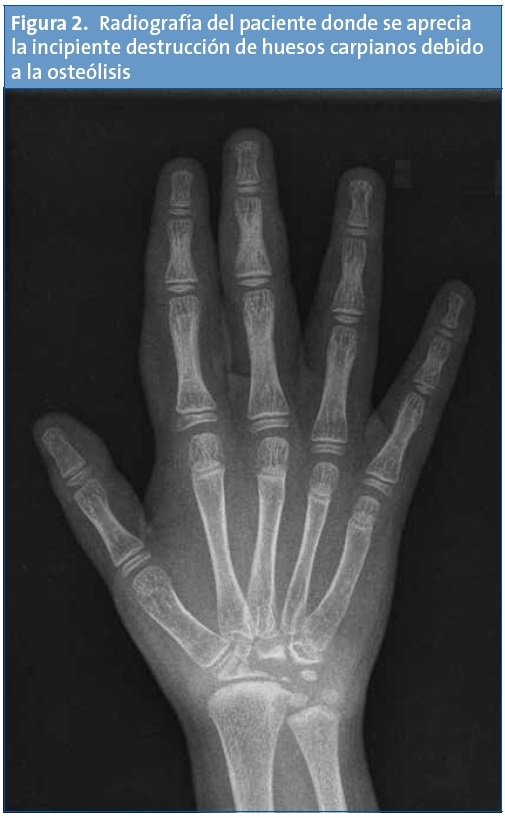

La radiografía del niño muestra lesiones carpales compatibles con osteólisis carpiana (Fig. 2) y lesiones en el escafoides tarsiano unilaterales.

La enfermedad se caracteriza por un inicio de los síntomas espontáneo, sin causas previas, en los primeros 2-3 años de vida, con inflamación y dolor a nivel de muñecas y pies. A este comienzo le sigue una rápida destrucción y reabsorción de los huesos afectados, siendo los carpianos y los tarsianos los que con más frecuencia se afectan. El resultado final suelen ser deformidades más o menos graves y la existencia de subluxaciones que pueden causar inestabilidad articular.